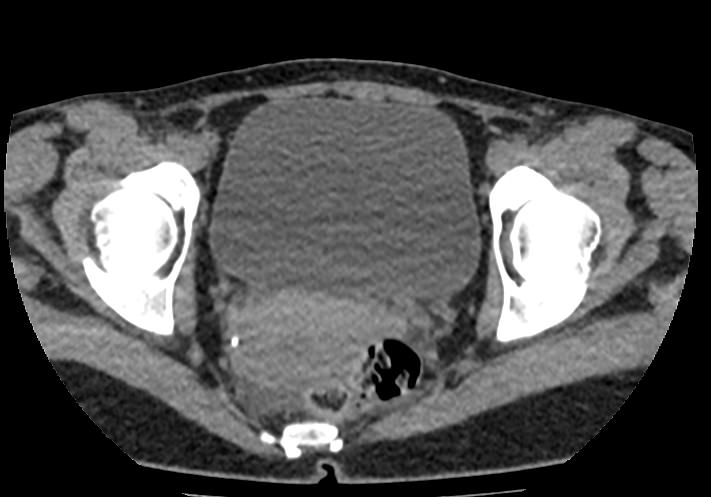

Мультиспиральная КТ мочевого пузыря является частью протокола обследования органов малого таза. Это высокоинформативный рентгенологический метод исследования, позволяющий детально визуализировать мочевой пузырь, нижнюю часть мочеточников, внутренние половые органы, прямую кишку.

Зачастую подобное исследование проводится при мочекаменной болезни (МКБ) для выявления конкрементов, определения их положения, размеров и плотности. Локализация конкремента существенно влияет на терапевтическое лечение МКБ, а наличие дивертикулов стенки мочевого пузыря на возможность самостоятельного выхода камня.

Также при данном исследовании возможно выявить утолщение стенки мочевого пузыря, что при диффузных изменениях может соответствовать проявлениям цистита, а локальные или неравномерные утолщения – характеризовать патологический процесс обусловленный новообразованиями.

Для улучшения визуализации патологических образований, в частности, при подозрении на опухолевый процесс, проводится внутривенное болюсное контрастирование. Методика контрастного усиления основана на введении в вену контрастного препарата, который в большей степени накапливается в патологически измененных участках и обеспечивает их яркую визуализацию на фоне здоровых тканей. Контрастирование дает возможность определить врачу границы опухоли, оценить степень прорастания в соседние органы и ткани, выявить опухоли минимальных размеров (как первичного, так и метастатического характера).

Что позволяет увидеть КТ мочевого пузыря

- цистит;

- дивертикулы мочевого пузыря

- цистоцеле

- уретероцеле

- варианты строения мочеточников

- камни мочевого пузыря;

- травмы, разрывы и растяжения органа;

- опухолевые новообразования.